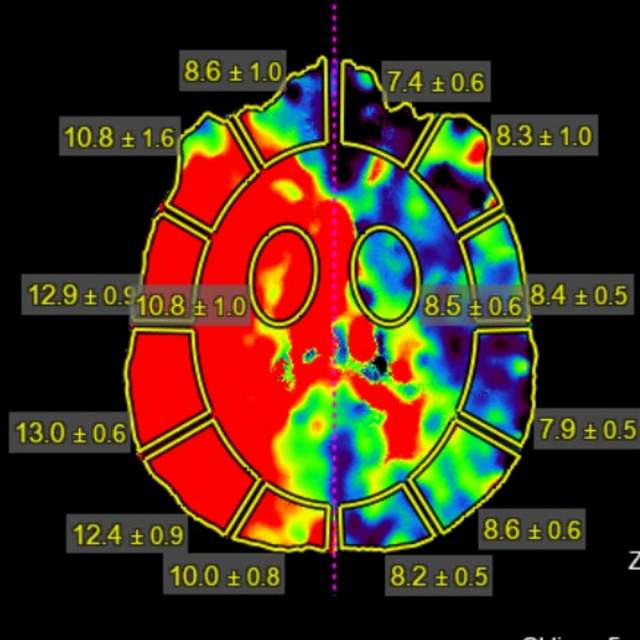

78岁老年男性,最近一个半月来已经和家里人没法正常交流,认知能力大幅下降,在农村,可能也就认为年龄大了,听天由命了。可老人家就是福大命大,有亲戚做医生,间隔17天先后为老人做了两次头颅MRI,发现脑梗塞,右侧血管长节段严重狭窄,右侧大脑半球缺血严重(图6,满江红),手术风险大……,家属经过反复咨询、犹豫、权衡,选择了保守治疗,毕竟老人年龄大了,手腿现在还能动,手术也有风险,时机也不是太好,国外研究不推荐,国内研究也不支持,保守治疗似乎是个不错的选择。然而,保守期间,患者反复出现脑梗塞,认知能力进行性下降,最终促使家属决定采用外科干预。然而,对医生而言,在梗塞的急性期处理这种长节段密布分支血管的病变风险不言而喻,而一味的观望和等候肯定不是最佳选择。过一点,可能出血;欠一点,可能闭塞。全面认真评估后,我们顺利为老人家完成了I期治疗,老人家的“火焰山”(图6)变成了“绿油油”充满生机的田野(图14),缺血明显改善,认知能力大幅提高,术后就能和家人正常交流了,也记起了很多以前忘记的事情……,家人很开心。